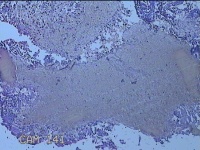

宫腔内容物

性别

女

年龄

47岁

临床诊断

1.异常子宫出血 2.慢性宫颈炎

一般病史

不规则阴道流血21天。

标本名称

大体所见

灰白暗红色不规则碎组织2.5x1.8x0.3cm一堆。

图3